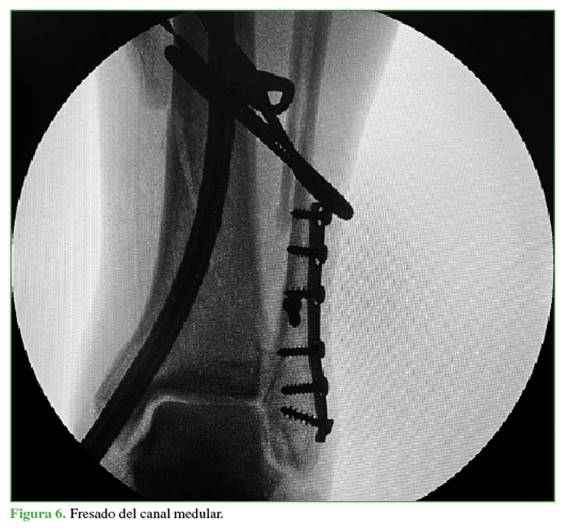

A continuación, se crea un abordaje de 3 cm desde la punta de maléolo tibial hacia distal (Figura 2). Mediante una clavija se ubica el sitio de ingreso en el centro del maléolo tibial, en ambos planos (Figuras 3 y 4), para luego agrandar con una fresa canulada la zona de ingreso (Figura 5), después se coloca una guía olivada (Figura 6) y, a través de un protector de partes blandas, se fresa el canal medular (Figura 7).